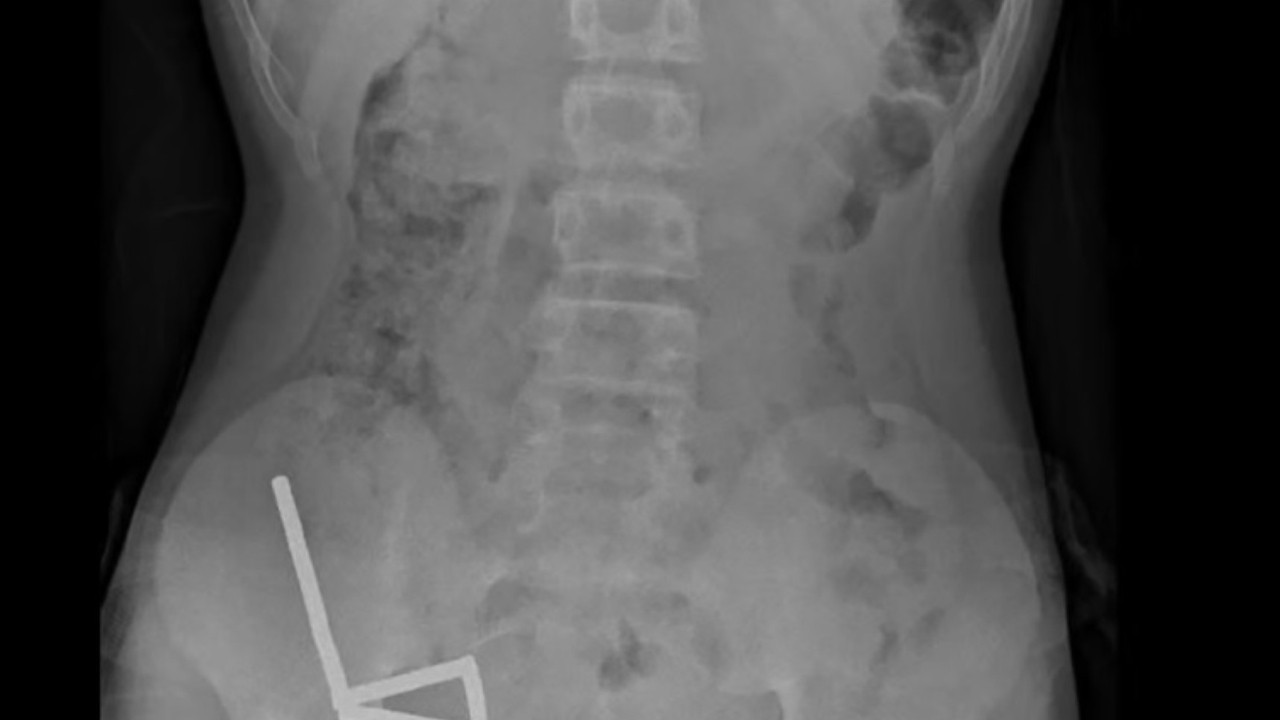

Çekilen röntgenlerde, mıknatısların çocuğun bağırsaklarında dört ayrı düz çizgi halinde kümelendiği ve “manyetik kuvvetler nedeniyle farklı bağırsak bölümlerinin birbirine yapıştığı” tespit edildi.

Doktorlar, mıknatısların neden olduğu hasar nedeniyle çocuğun bağırsağının bir bölümünü ve mıknatısların çıkarıldığını açıkladı.